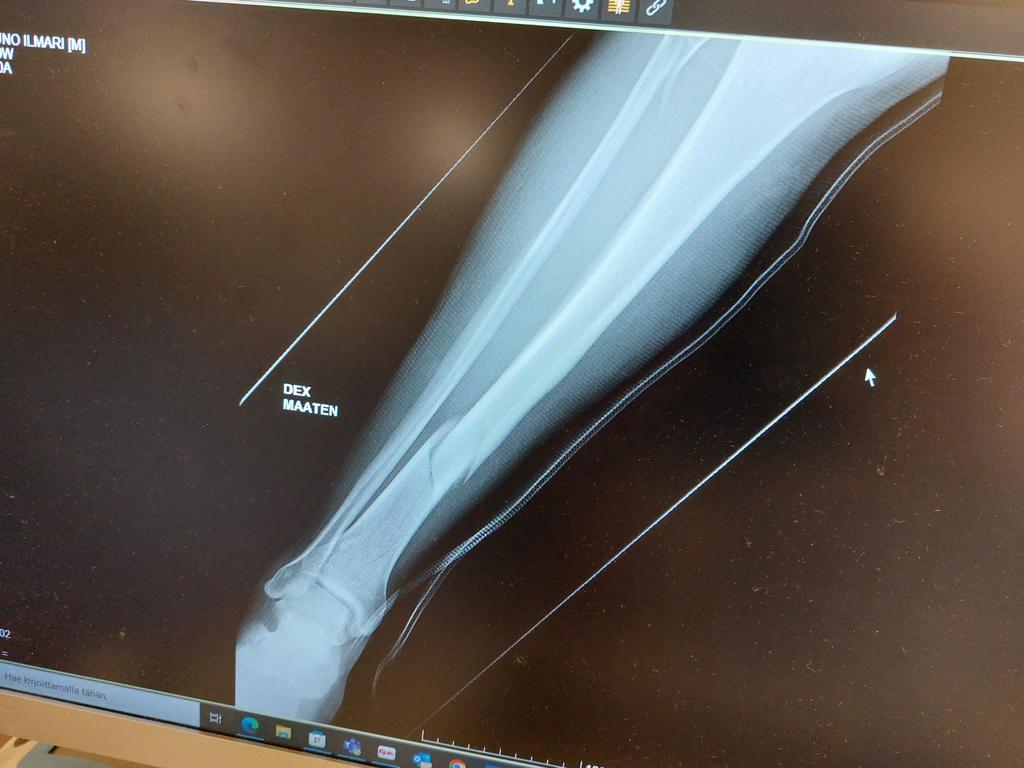

Aloitan jalkani telomisesta.... :(

Poikki on ja eiku leikkaukseen...